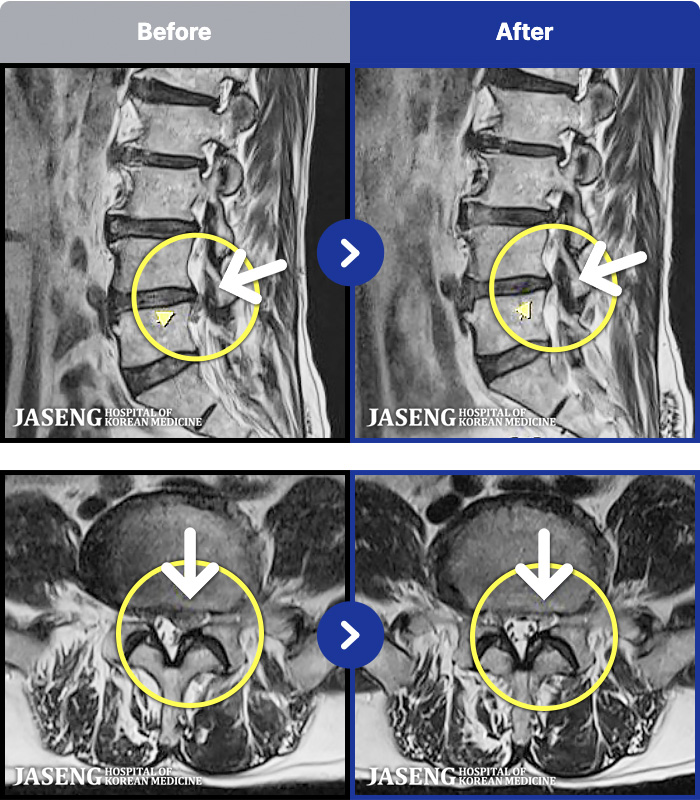

MRI ġ

1,304 MRI ũ ʸ Ȯϼ.